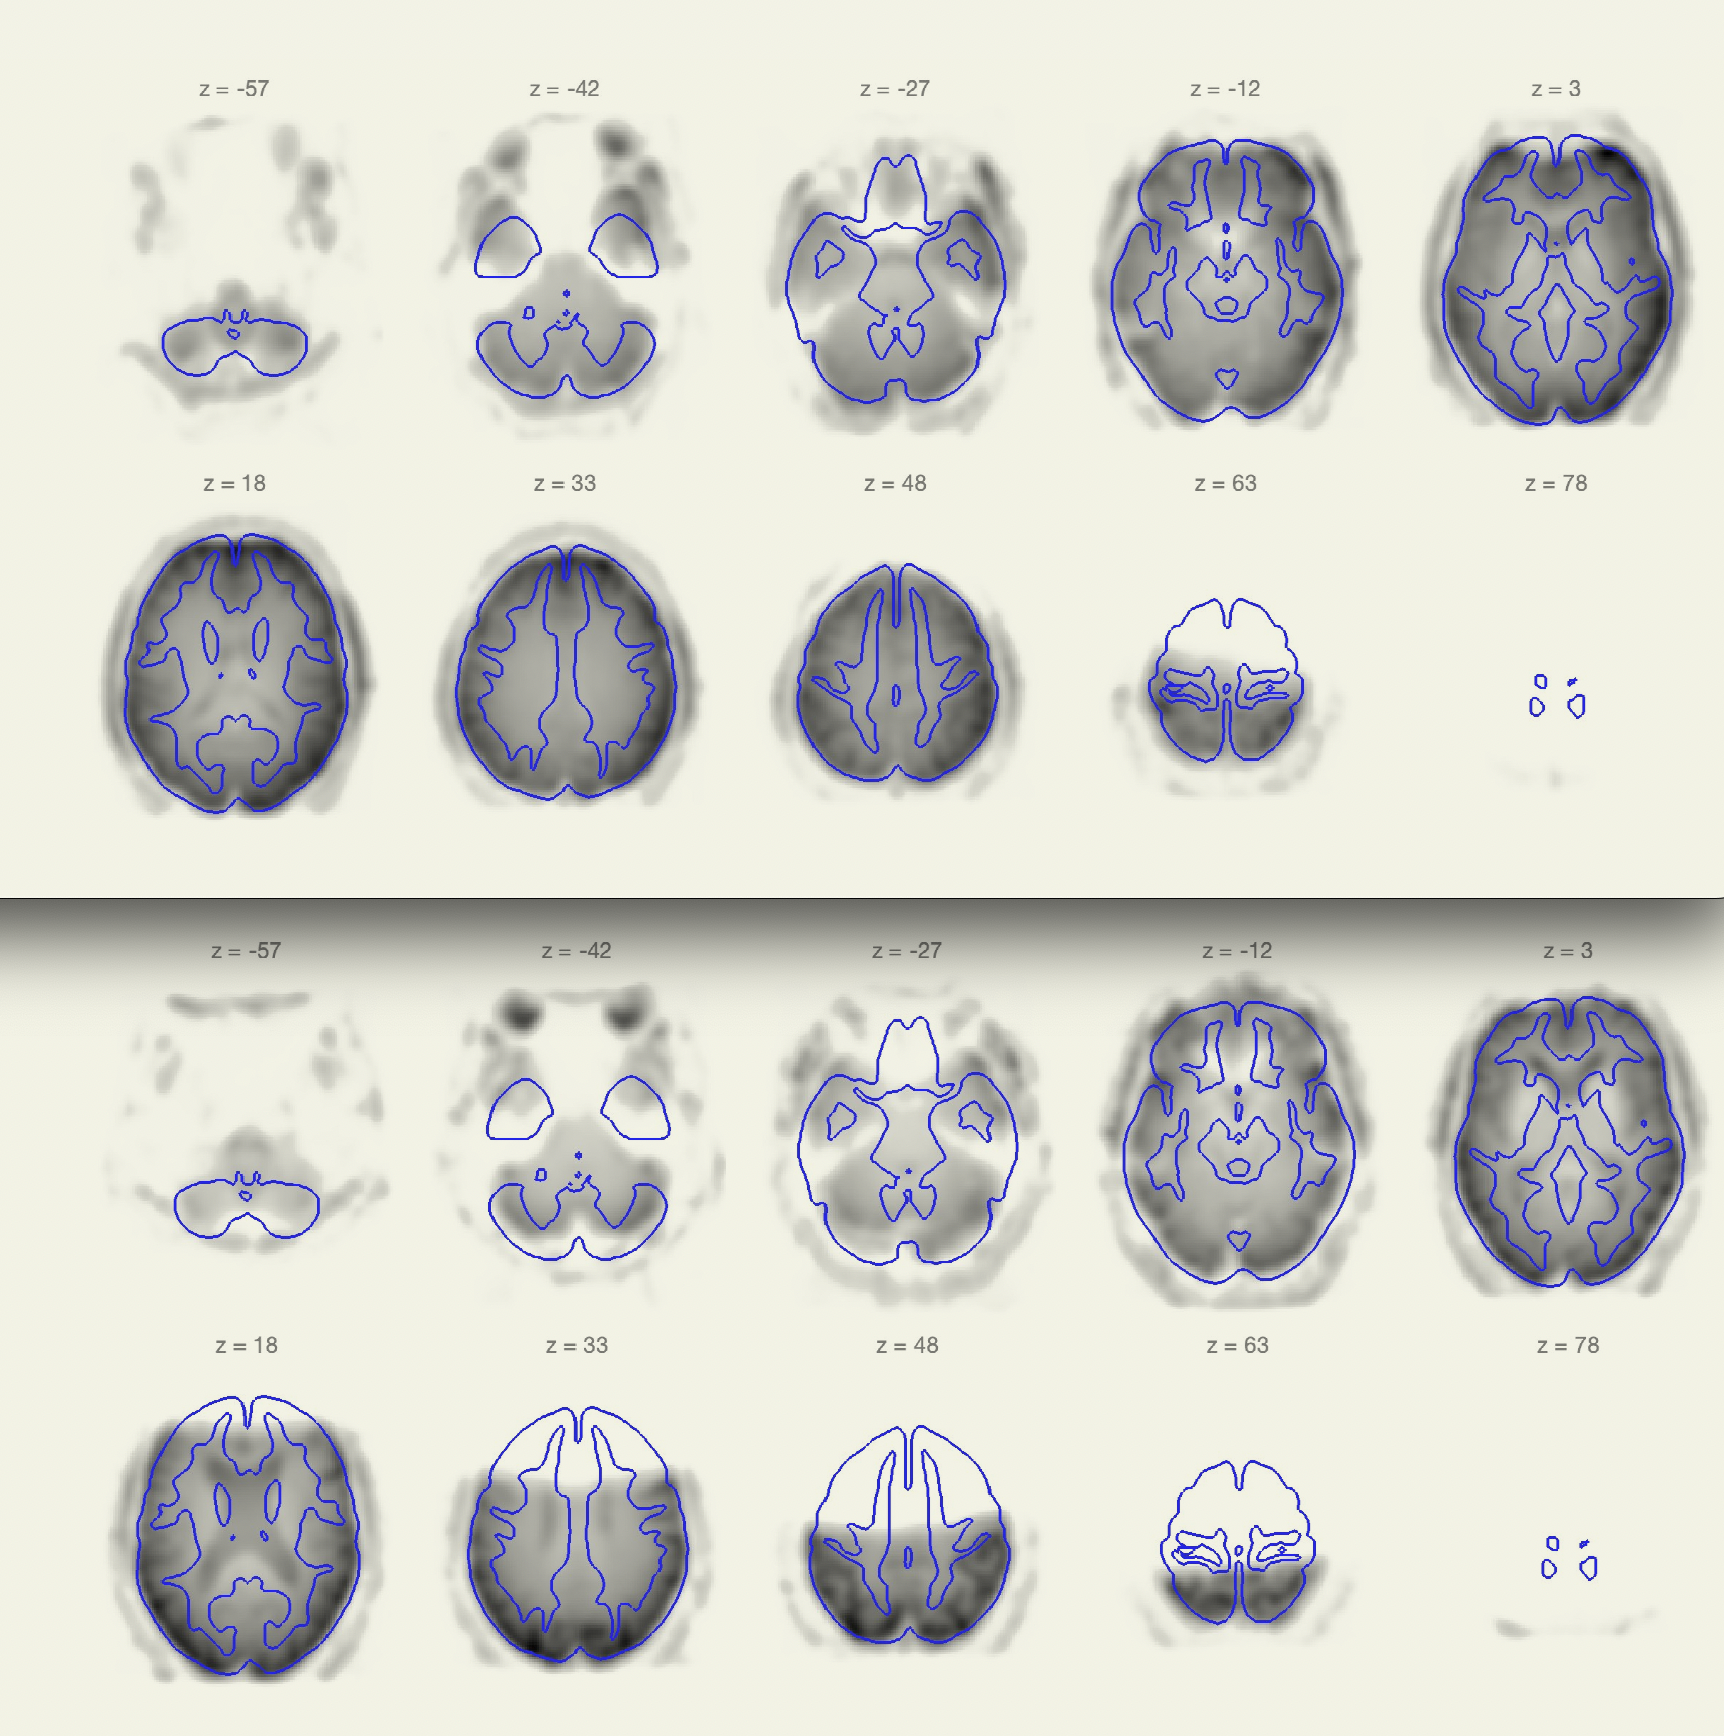

Thanks so much for getting back to me. I checked the functional normalization plots, like you suggested, and I do see the problem there (see attached screenshots for the same two subjects I shared photos of in my first message). What do you recommend as the best way to fix this??